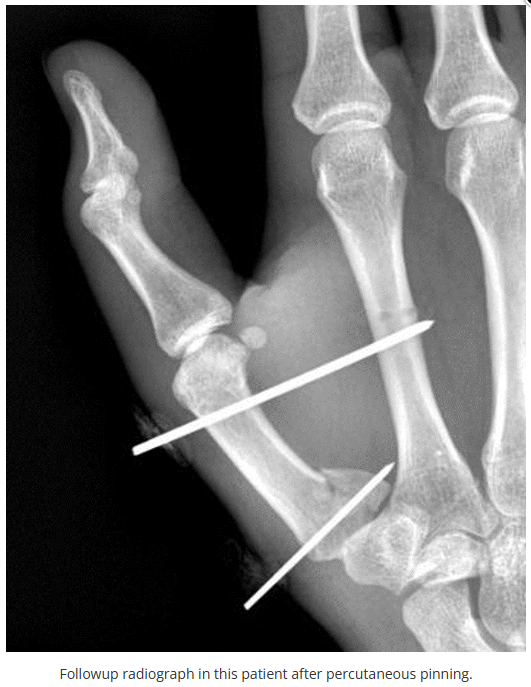

今天是腕部与手的X线片。所有X线片都

带有标注和说明

,可以选择长按图片,

自动翻译相关说明